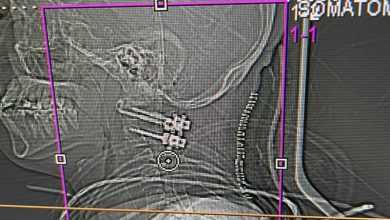

عملية جراحية معقدة لتعديل العمود الفقري في مستشفى “دله نمار” تُغَيّر حياة مريض عشريني

أعلنت مستشفى “دله نمار”، عن إجراء عملية جراحية معقدة ومتطورة لتعديل العمود الفقري لمريض يبلغ من العمر 26 عامًا؛ حيث…